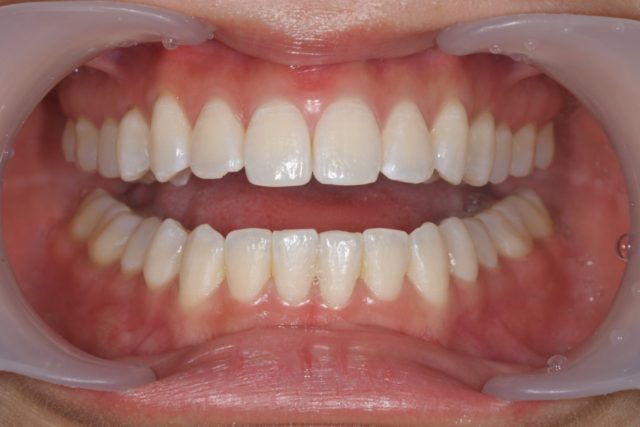

①お口を閉じたときの正面のお写真

普段お口を閉じている位置でしっかり奥歯で噛んで頂きます。

このお写真で、普段どこで噛んでいるかという噛み合わせを診ていきます。